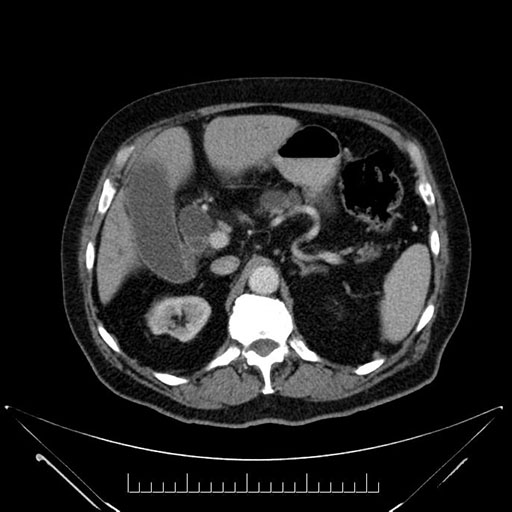

Whipple (pancreaticoduodenectomy) [case 7]

Imaging Analysis

Look through the patient's CT scan to identify any areas of concern for the necessary procedure.

Based on your CT findings, which issue(s) would give reason for "planned slowing down moment(s)" in this case?

Considering a standard Whipple procedure, what step(s) of the operation would you do differently in this case?